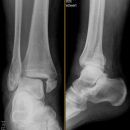

Sprunggelenk

Weber A

Es wurden keine Bilder gefunden.

Weber B

Weber C + dorsales Volkmann

Trimalleoläre

Vorderes Volkmann + lat. Talusschulter